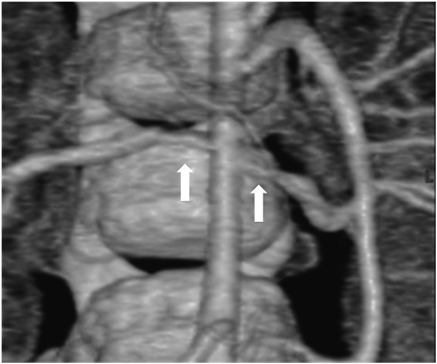

Her state was stable without particular interventions until echocardiography showed the signs of right heart failure at six days after birth, and we began diuretics (furosemide [1 mg/kg/day] and aldactone [1 mg/kg/day]). She was discharged at twenty days after birth since SVAS and PPS did not proceed. She was a normal psychomotor development, smiling at two months old, head controlling at four months old, sitting at seven months old and crawling at nine months old. The distinctive facies and the undeveloped recognition were not seen in follow-up periods. At ten months old, she was hospitalized and received cardiac catheterization for consideration of treatment policy. Cardiac catheterization revealed that the pressure gradient was right atrium-right ventricle, bilateral peripheral pulmonary arteries-main pulmonary artery and left ventricle-ascending aorta. Estimated pressure gradient between left ventricle and ascending aorta was 40 mmHg and cardiac contractility was sufficient (Table 1), so we decided to manage her without surgical interventions. For hypertension, we performed Multi Detector-row Computed Tomography and discovered bilateral renal artery stenosis (Fig. 2). She had high renin/angiotensin ratio (plasma renin activity was 59.5 ng/mL/hr [reference range; 0.2–2.7 ng/mL/hr] and plasma aldosterone concentration was 128 ng/dL [reference range; 2–13 ng/dL]), and we diagnosed her renovascular hypertension and started carvedilol.

Fig. 2 Multi detector-row computed tomography

Bilateral renal artery stenosis is observed (arrow).